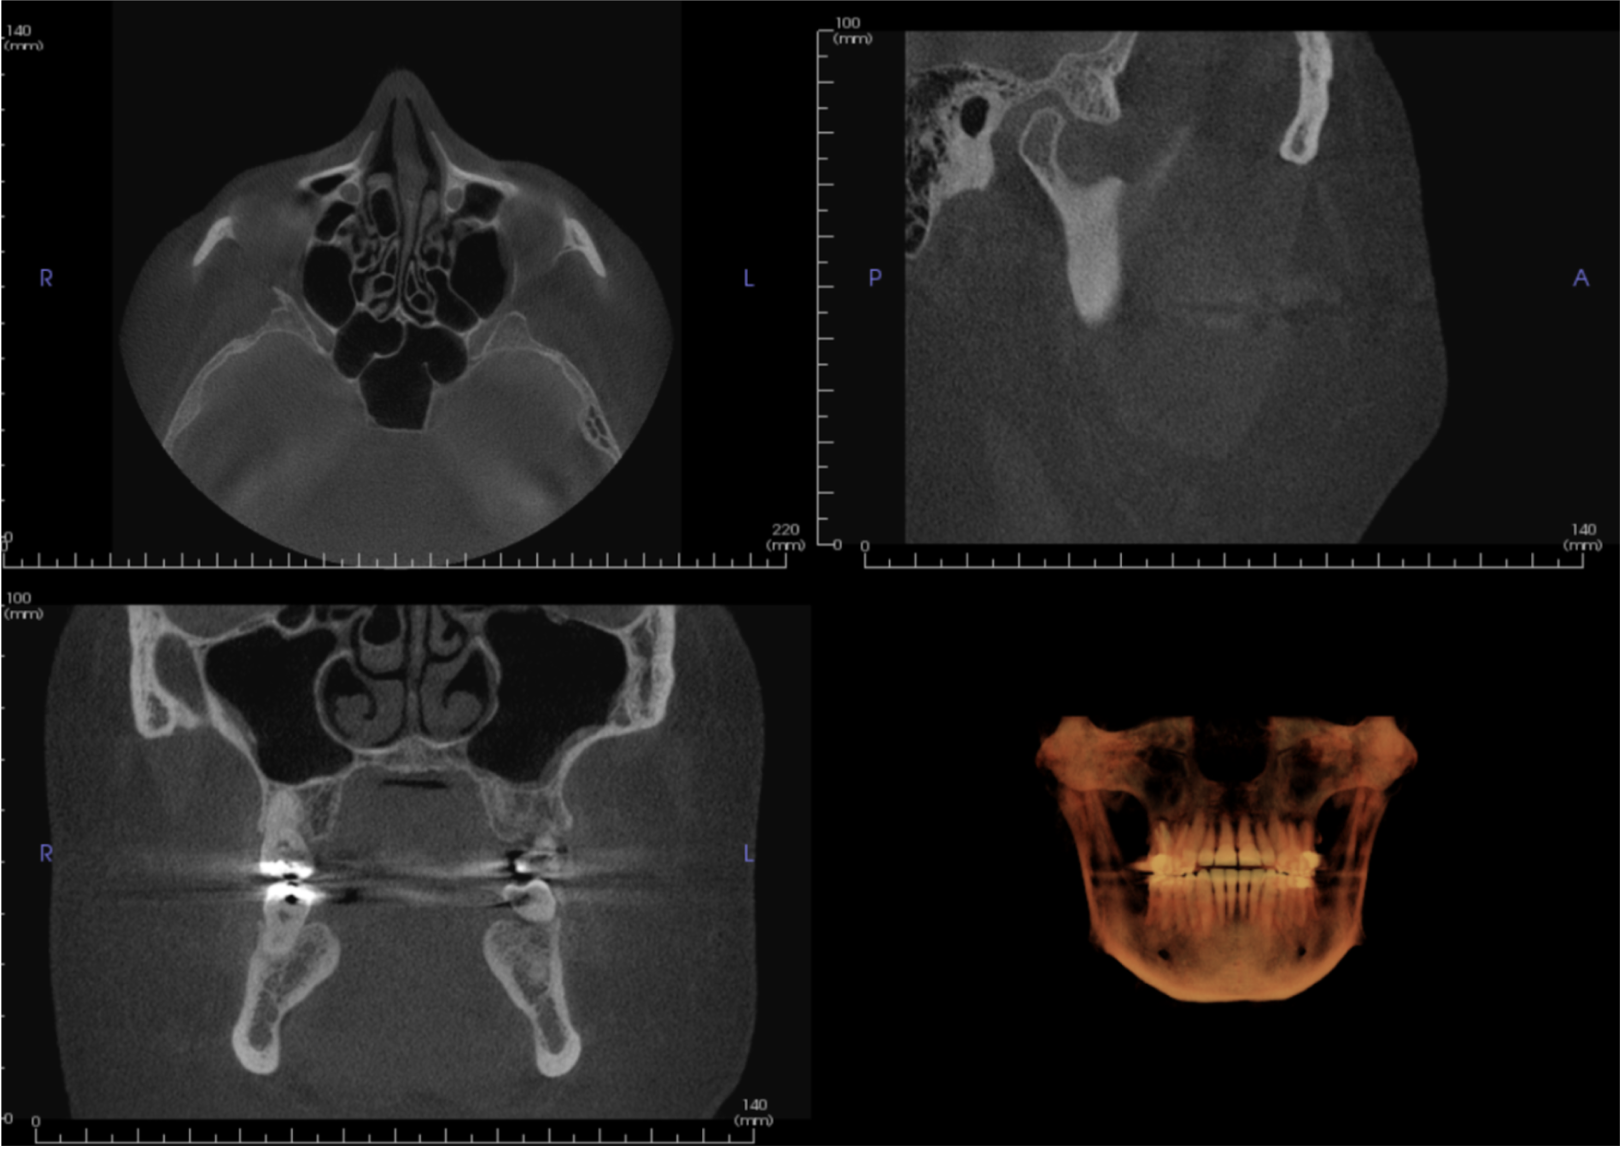

CBCT Imaging Evaluation